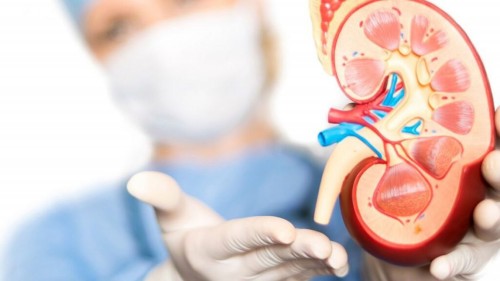

1. What is Kidney Failure?

Kidney failure occurs when the kidneys can no longer perform their functions effectively, such as filtering metabolic waste, maintaining fluid balance, and regulating electrolytes in the body.

Kidney disorders in children generally occur in two main forms:

- Acute Kidney Injury (AKI)

AKI is a sudden decline in kidney function that can develop within hours or days. It may be caused by severe infection, dehydration, exposure to toxins, or side effects of certain medications.

- Chronic Kidney Disease (CKD)

Chronic kidney disease refers to kidney damage lasting more than three months and can gradually reduce kidney function permanently.